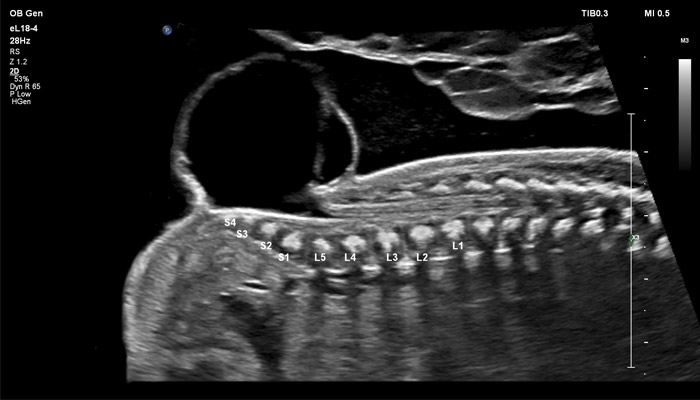

Применение eL18-4 в I триместре беременности

Линейный матричный датчик eL18-4 позволяет получить детальную информацию об анатомии плода и выявить пороки на ранней стадии развития. Сверхширокополосная PureWave матрица датчика генерирует частоты в диапазоне 2-22 МГц, что формирует одинаково высокоинформативные, четкие изображения по всей глубине сканирования до 14 см.

Высокочастотный датчик Philips eL18-4 содержит решетку из 1920 активных монокристаллических пьезоэлементов, выполненных по усовершенствованной технологии PureWave. Это обеспечивает высокодетальную 2D визуализацию, которая в совокупности с глубиной сканирования необходима для уверенной диагностики в акушерстве.

До введения высокочастотных линейных датчиков точная ультразвуковая диагностика мочевой системы плода была доступна в основном после 16-17 недель беременности. Новая технология еL18-4 позволяет проводить раннюю морфологическую оценку плода уже в первом триместре. Клинический случай с применением eL18-4 демонстрирует, что кортико-медуллярная дифференцировка почек плода возможна на 14 неделе беременности”.

В случае аномалий позвоночника, оценка ануса важна, чтобы исключить аноректальные пороки развития, которые могут быть частью более широкой группы аномалий, известных как VACTERL (аномалии позвоночника, атрезия ануса, пороки сердца, трахеопищеводный свищ, аномалии почек, дефекты лучевой кости). Исследования в США показали, что очень высокое качество изображений еL18-4 повышают уверенность клиницистов в исключении аноректальной аномалии плода.

Использование линейного матричного датчика eL18-4 при осмотре беременных в I триместре, особенно на ранних сроках, позволяет ограничиться трансабдоминальным сканированием вместо трансвагинального и при этом получить максимально полную диагностическую информацию. Отсутствие полостного исследования чрезвычайно важно для соблюдения принципа ALARA – использования минимальной необходимой мощности для безопасности пациента. Благодаря применению мультичастотного датчика с диапазоном от 2 до 22 МГц через переднюю брюшную стенку хорошо определяется эмбрион длиной 3 мм, что соответствует шестой неделе беременности. В конце I триместра с eL18-4 достаточно отчётливо визуализируется четырёхкамерный срез сердца, мочевой пузырь и сосуды пуповины, которые, как правило, определяются только при трансвагинальном сканировании.

Во II триместре беременности высокая разрешающая способность eL18-4 позволяет детально изучить структуру органов и тканей и увидеть многие нюансы, которые при работе другими датчиками не обнаруживались или становились очевидны в более поздние сроки. Например, у 19-недельного плода визуализируется перегородка носа, мышцы языка, диафрагма между грудной и брюшной полостью, на 20-й неделе чётко определяются оболочки спинного мозга и уретра, а на 24-й – хорошо дифференцируются корень лёгкого, борозды и извилины мозжечка и многие другие структуры.